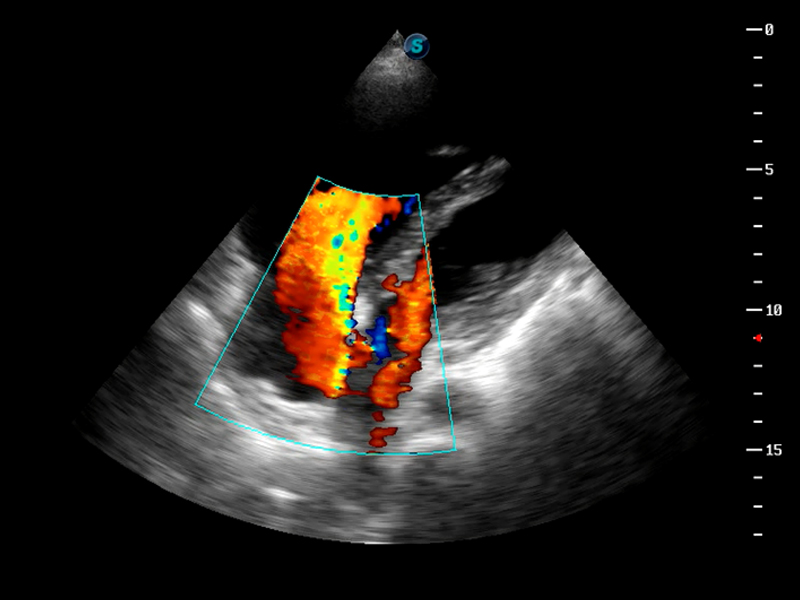

心脏房间隔缺损血流